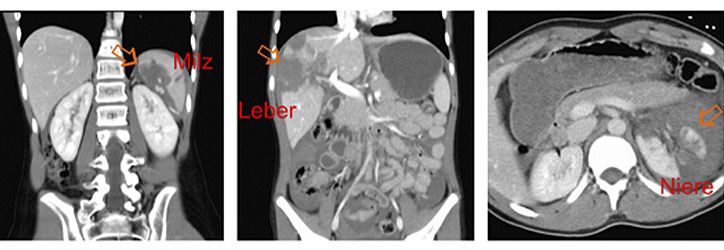

Die Bauchorgane werden in Europa fast ausschließlich durch stumpfe Traumen verletzt. Die Unfallursachen sind altersabhängig und bei Kleinkindern v.a. Stürze, bei Schulkindern zunehmend Sportunfälle und in allen Altersgruppen Verkehrunfälle. Am häufigsten sind Milz, Leber und Nieren (Abbildung) verletzt, seltener die Bauchspeicheldrüse oder der Magen-Darm-Trakt.

Bei Kindern gibt es die Besonderheiten einer noch schwach ausgebildeden Muskulatur des Bauches und flüssigkeitsreichere Organe, die relativ gesehen größer sind als bei Erwachsenen. Führendes Leitsymptom beim Bauchtrauma ist der Bauchschmerz, es können aber auch Übelkeit und Erbechen vorliegen. Wichtig ist zu unterscheiden zwischen isoliertem Bauchtrauma und Patienten mit Mehrfachverletzungen/Polytrauma.